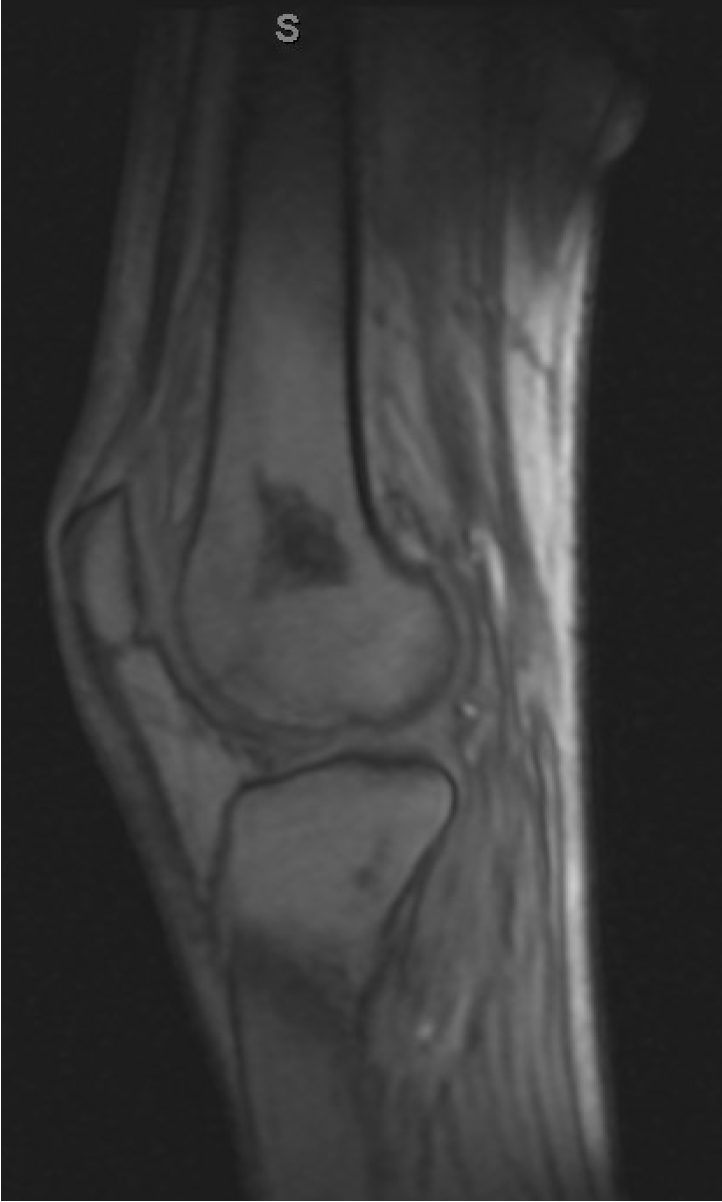

Case Presentation: A 48-year-old man with end-stage renal disease due to IgA nephropathy underwent a deceased donor kidney transplant in 2008, which resulted in graft failure. A second transplant in 2019 required additional thymoglobulin due to high panel reactive antibodies and was complicated by BK nephritis, treated with leflunomide. Since treatment, he had persistent leukopenia, absolute lymphocytopenia and had been on chronic immunosuppressive therapy with mycophenolate, tacrolimus and prednisone. He presented with an eight-month history of oropharyngeal pain, odynophagia, significant 30-pound weight loss, and progressive right ankle pain. Examination revealed white plaques and two shallow ulcers with erythematous borders on the tongue; his ankle had marked swelling and tenderness. Initial treatment for suspected oropharyngeal and esophageal candidiasis failed. Tests for HIV , CMV , EBV , and BKV, were negative. Laryngoscopy showed asymmetric tongue base fullness; EGD was unremarkable. A biopsy of the tongue lesion eventually revealed intracellular fungal elements consistent with Histoplasma capsulatum, prompting a positive quantitative urine Histoplasma antigen (1.6 ng/mL). Patient was then admitted for further treatment and imaging. A CT scan showed a calcified granuloma in the right lung and bilateral adrenal nodules measuring 15 and 11mm, while an MRI revealed ankle and knee tenosynovitis. The lung granuloma was presumed to be the site of latent infection, with additional findings indicative of disseminated disease. Treatment included prednisone for physiological adrenal replacement, posaconazole, and discontinuation of mycophenolate, leading to significant improvement. However, new left knee tenosynovitis developed ten days into treatment. The patient’s urine antigen levels decreased by 50%, and he was discharged with a plan to complete 12 months of antifungal therapy, depending on clinical evolution and follow-up.